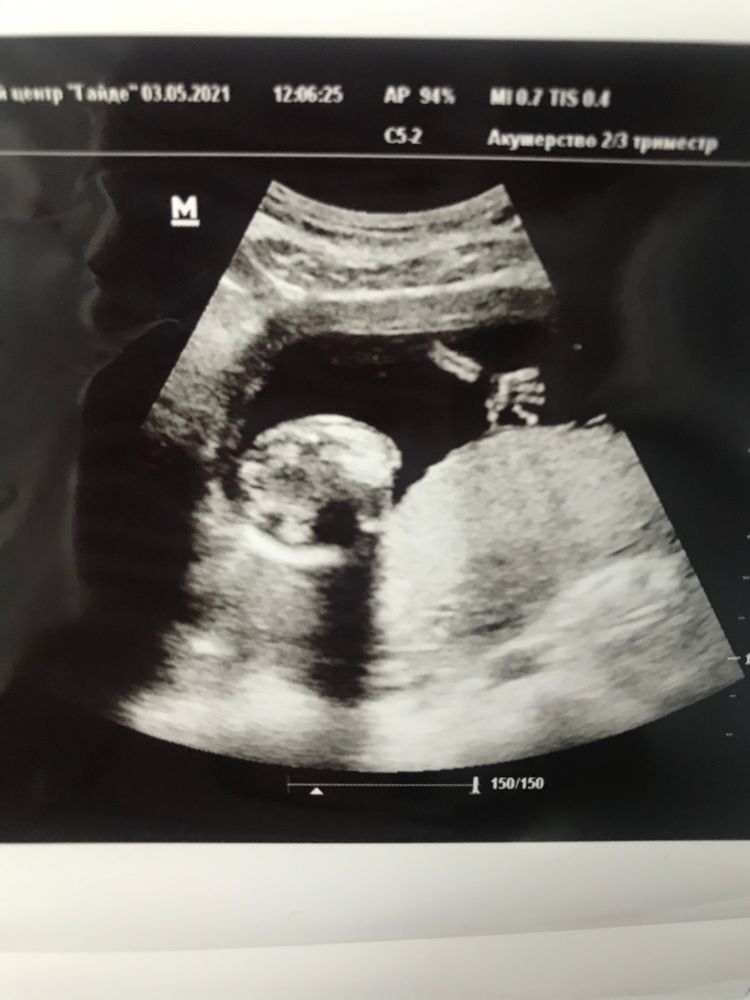

Сходила на платное УЗИ сегодня 🤗

Здравствуй, ещё одна глазастая принцесса 👸🏻 😍 Да-да, врач так и сказала - большие какие глазки у малышки🥰 Про Златославу тоже сразу сказали тогда - большеглазая будет, так и есть. Это у нас семейное ☺️😌

По УЗИ всё всё хорошо 👌🏻